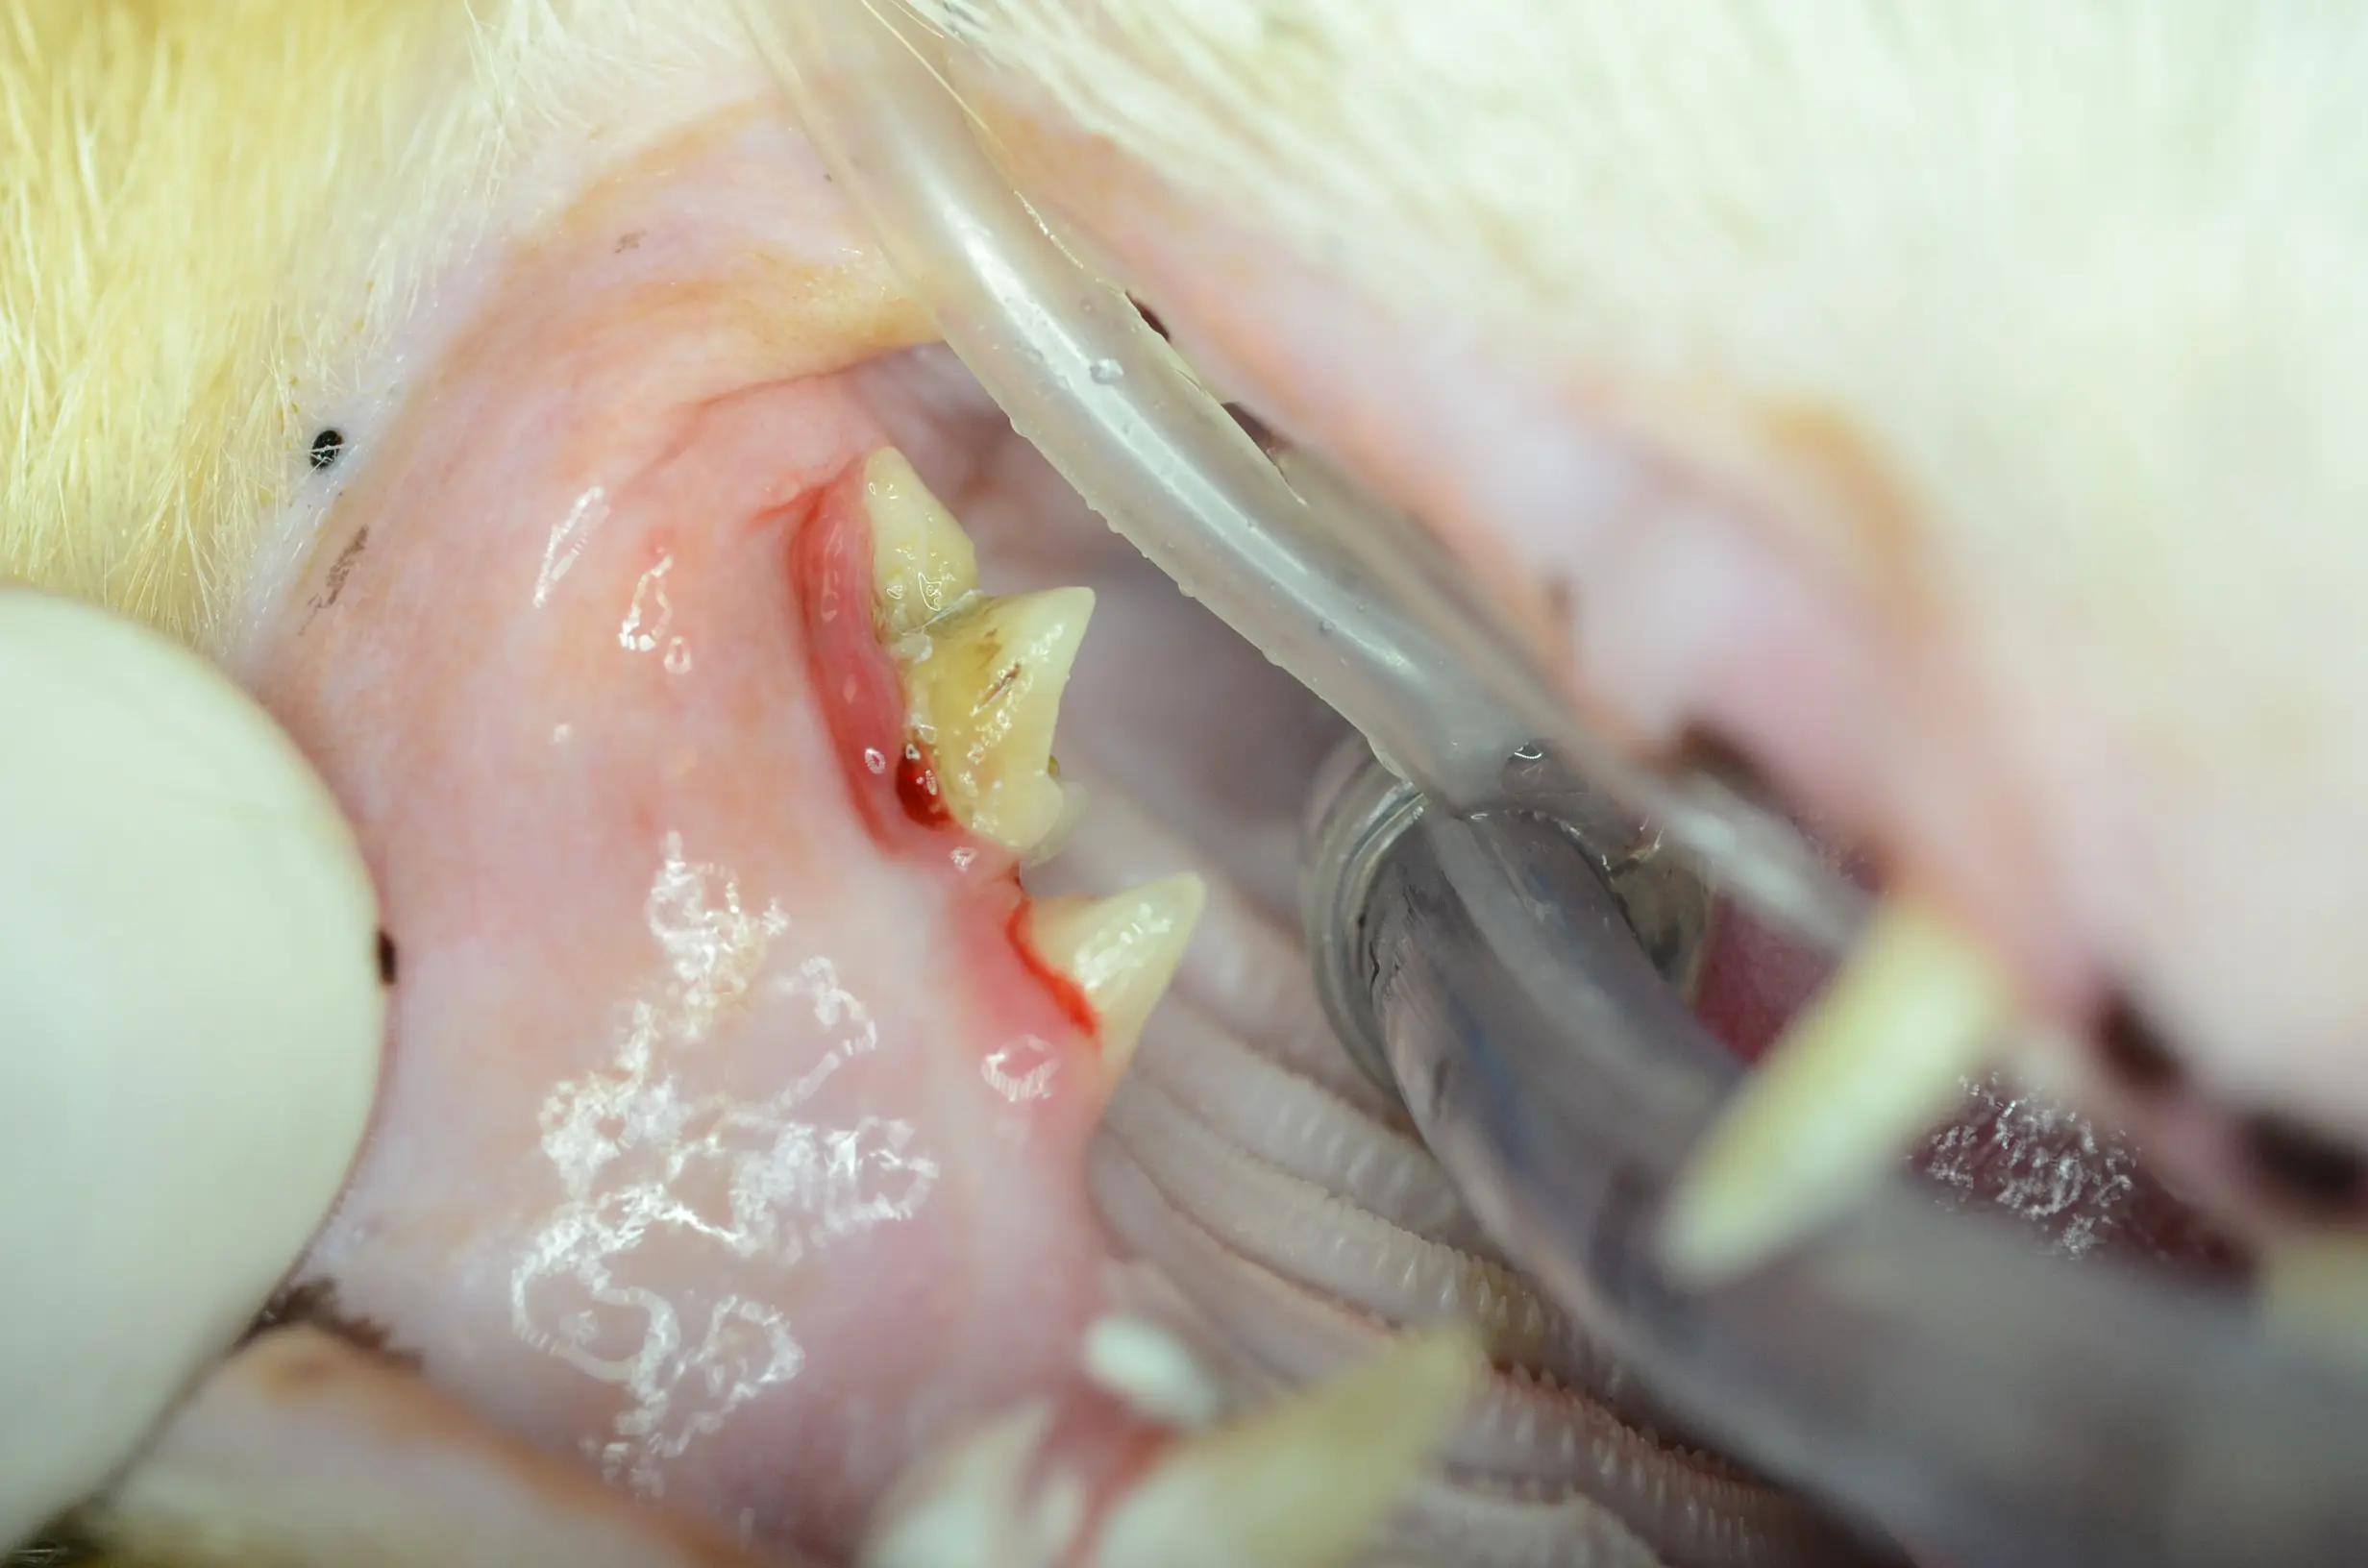

Post-extraction images:

Histopathology results: Chronic osteomyelitis and osteolytic remodeling of alveolar bone expansion. No evidence of neoplasia.

Comments: Swelling due to osteomyelitis can occur secondary to tooth resorptions and/or chronic periodontitis. This is referred to as expansile or alveolar osteitis. If you treat the underlying pathology, this resolves. However, knowledge of how to perform alveoloplasty post-extractions with proper flap design is imperative. Therefore, chronic swelling in an older cat should be worked up both radiographically and histopathologically to get a proper diagnosis. While tumors do occur in older cats, this individual outcome was quite favorable and this cat returned to a very happy lifestyle.